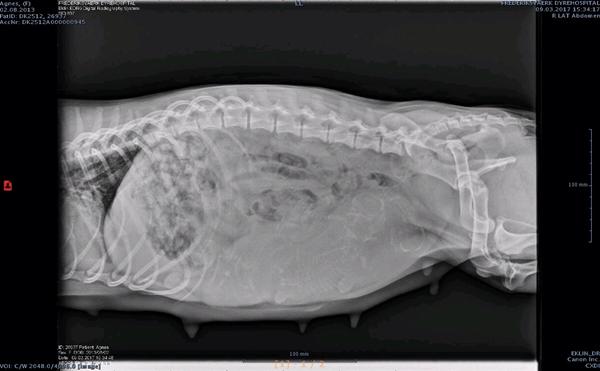

Hvor ser man hvalpene på sådan et scanningsbillede?

Hvor "ligger" hvalpene så på billedet?

så kan jeg måske bedre vide hvad jeg skal kigge efter næste gang.